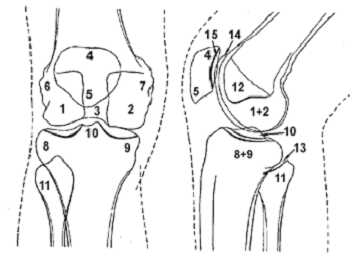

Стандартные проекции, применяемые при рентгенографии коленного сустава – прямая (передне-задняя) и боковая (рис.1). По мере необходимости их дополняют правой или левой косой, а также аксиальной проекциями. Основным правилом при рентгенологическом исследовании коленного сустава является полипозиционность.

Рисунок 1. Проекции, применяемые при рентгенографии коленного сустава.

Схема к рисунку 1.

1. Латеральный мыщелок бедренной кости.

2. Медиальный мыщелок бедренной кости.

3. Межмыщелковая ямка.

4. Основание надколенника.

5. Верхушка надколенника.

6. Латеральный надмыщелок бедренной кости.

7. Медиальный надмыщелок бедренной кости.

8. Латеральный мыщелок большеберцовой кости.

9. Медиальный мыщелок большеберцовой кости.

10. Межмыщелковое возвышение.

11. Головка малоберцовой кости.

12. "Пятно" Людлофа.

13. Рентгеновская суставная щель большеберцово-малоберцового сустава.

14. Суставная поверхность (трохлея) головки бедренной кости.

15. Суставная поверхность надколенника .